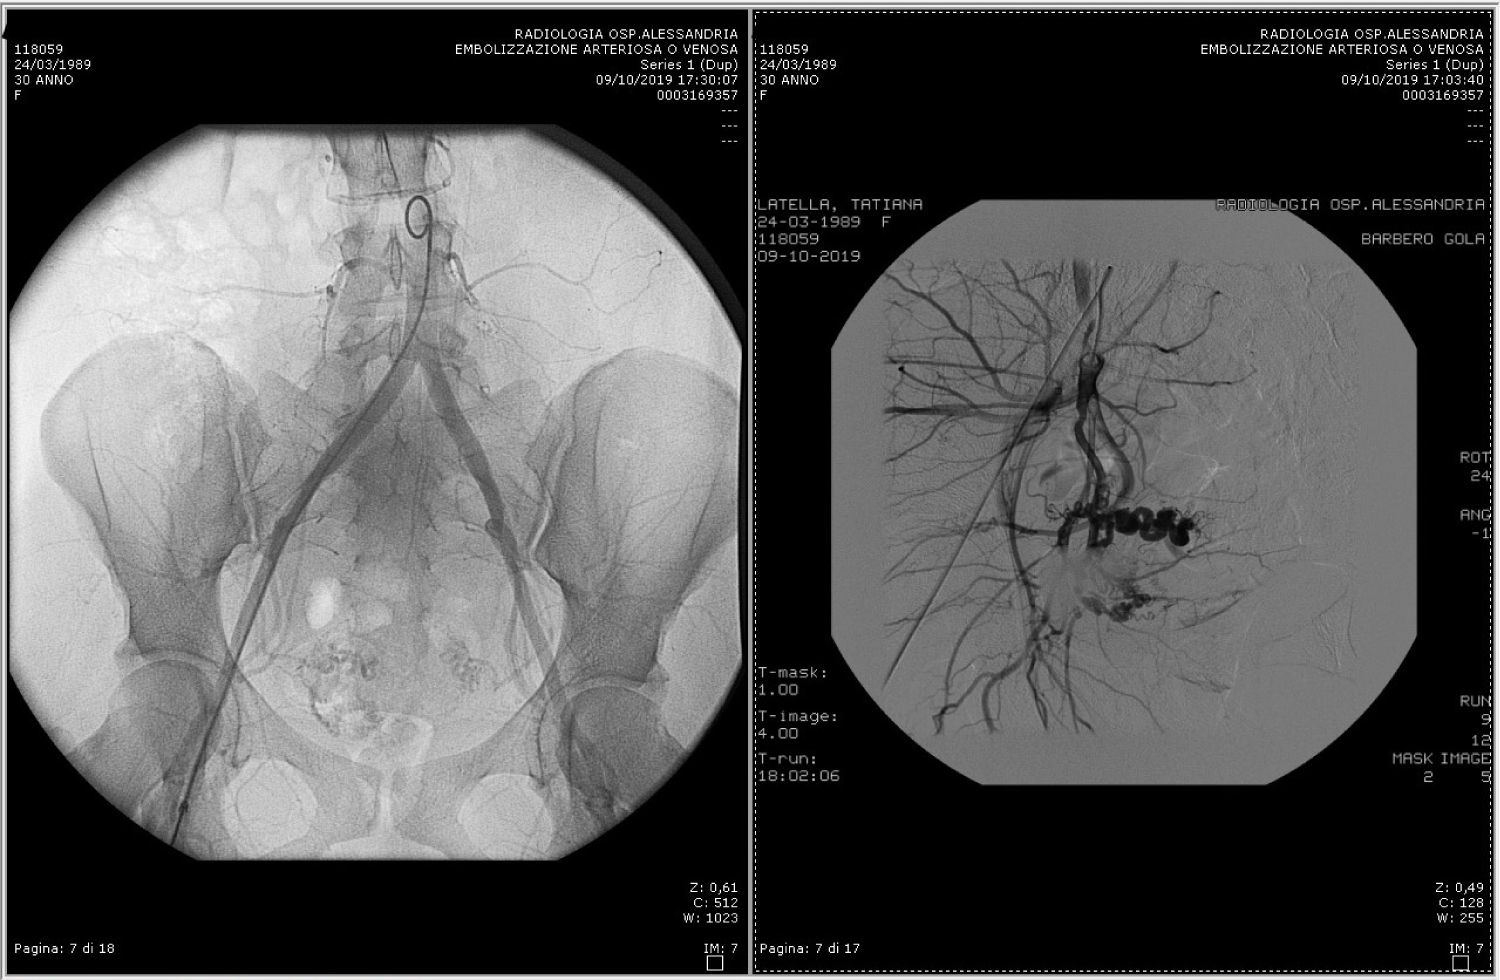

She had no menstrual period for 3 months until she went for a transvaginal ultrasound scan on October 2nd 2019, about three months after pregnancy termination. Beta-HCG assays showed values of 49.9 IU/L on September 6th, and of 30.7 IU/L on September 13th. Transvaginal sonography found a disomogeneous intrauterine mass with color score 3, suggestive of an intrauterine arteriovenous malformation. She was thus admitted to hospital on the day after. A second ultrasound scan was performed and the initial hypothesis was confirmed: A hypervascularized formation of about 30 mm was found inside the uterus. Its main feature was the presence of a low resistance arterial flow associated with large vessels with arterial pulsation (Figure 1). At admission the level of serum beta-HCG was of 8 IU/L, this excluded the hypothesis of a trophoblastic disease. On the days 5th and 6th of October she reported having some dark discharge which resulted in scarce vaginal bleeding.

Figure 1: Uterine arteriovenous malformation with high flow and arterial pulse at color doppler. View Figure 1